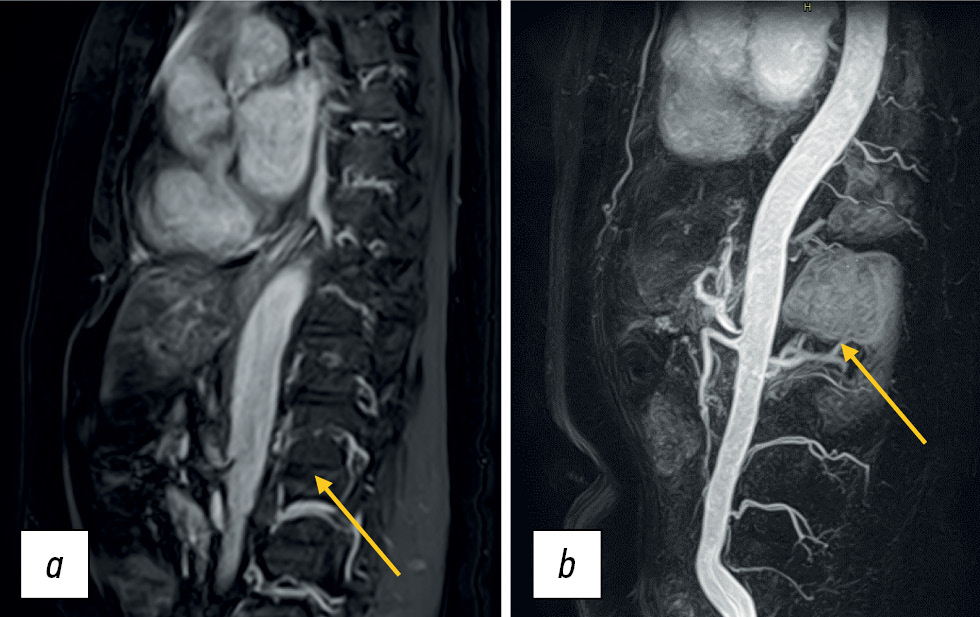

Dynamic pre- and postcontrast T1-WIs can be obtained using 2D or 3D pulse sequences [6], with 3D sequences preferred because minimizing slice thickness reduces truncation artifacts. 3D SGE sequences were initially used to visualize vascular anatomy (MR angiography; Fig. 8). This technique is currently widely used to visualize soft tissue structures in the abdominal cavity and small pelvis. Short repetition time and TE values allow for the acquisition of many thin sections in a single breath-hold. The relatively low SNR of this sequence may be a limitation; however, this disadvantage is offset by the use of intravenous contrast.

Figure 8. Contrast-enhanced magnetic resonance imaging of the abdominal aorta and its branches. Extravascular compression of the celiac trunk by crus diaphragm (arrows): а SSFE; b contrast-enhanced 3D mode.